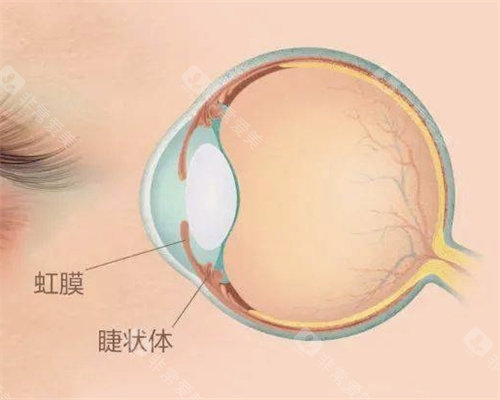

人工虹膜植入手术2025年更新价格已出炉,基础费用8万元起,海南博鳌超级医院与海口国爱眼科形成区域价格差。

博鳌超级医院采用德国HumanOptics虹膜假体,5D纹理复刻技术误差仅0.02mm。海口国爱主推美国定制虹膜,光敏感度调节功能溢价15%。